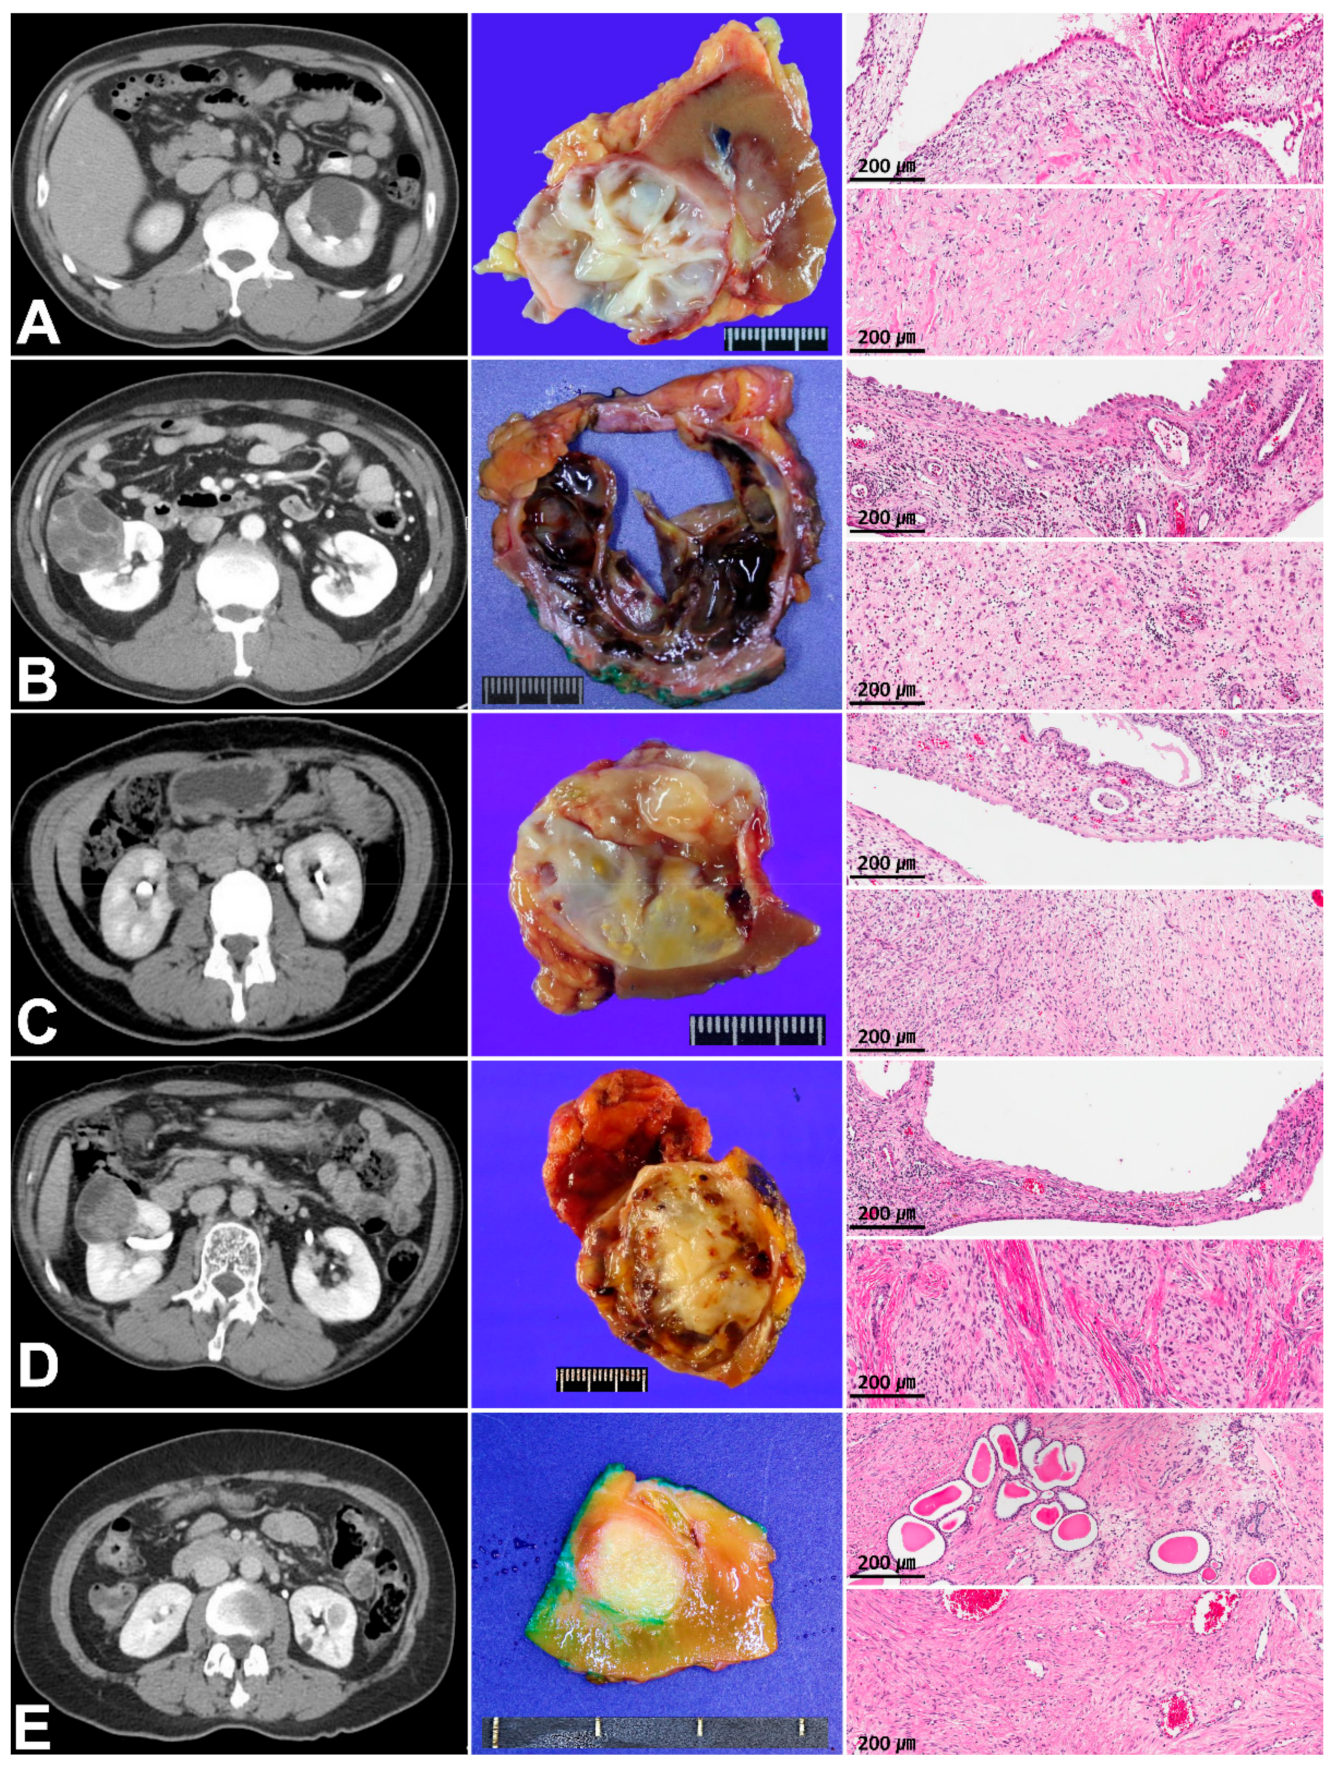

3.1. Clinicopathologic Characteristics and Immunoreactivity of the Five Cases of MESTK